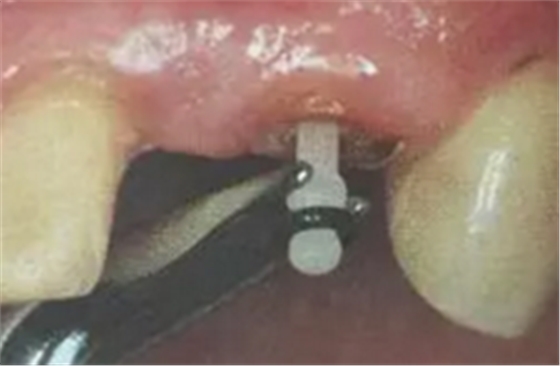

(超聲預(yù)備根管完成)

ELLIPSON 技術(shù),采用超聲預(yù)備鉆對扁圓形根管進(jìn)行直接預(yù)備,改善了樁核根管的適應(yīng)性。有效的保存了根管牙體組織,從而增強(qiáng)了粘接面積,,減少樹脂水門汀的厚度,提高根管內(nèi)纖維樁的粘接強(qiáng)度。

(插入橢圓形纖維樁)